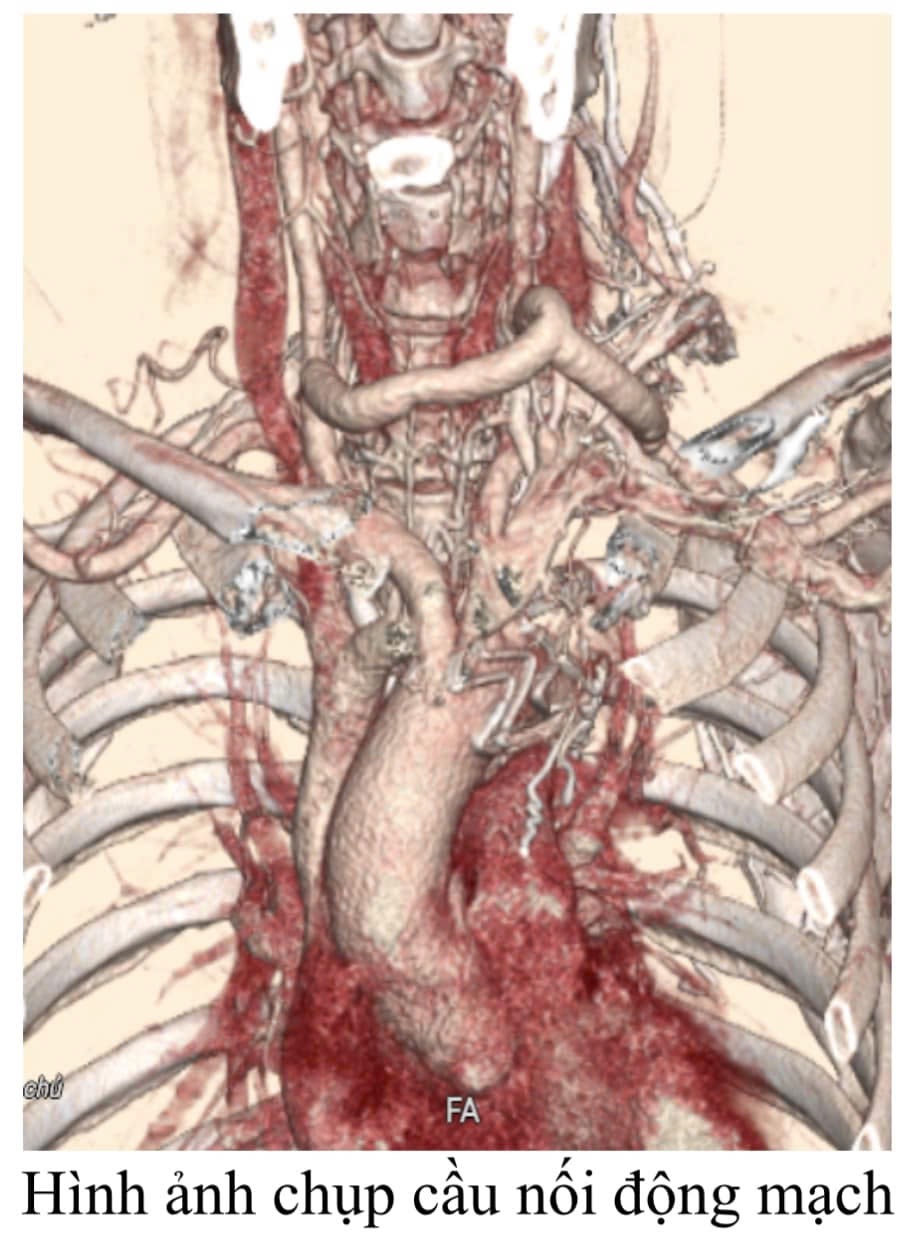

Trước tình trạng “ngàn cân treo sợi tóc” của bệnh nhân, các bác sĩ khoa Nội Tim mạch và khoa Phẫu thuật Thần kinh – Lồng ngực đã tiến hành hội chẩn khẩn cấp để đưa ra phương án điều trị cho người bệnh.Phương án tối ưu nhất được lựa chọn là phẫu thuật nối động mạch cảnh – cảnh, động mạch cảnh – dưới đòn trái để mở rộng vị trí đặt Stent Graft sau đấy sẽ tiến hành đặt Stent Graft.

Chỉ trong vòng 1 giờ sau hội chẩn, ê-kíp phẫu thuật mạch máu đã khẩn trương tiến hành phẫu thuật bắc cầu động mạch thành công. Ngay sau đó, Stent Graft đã được các bác sĩ can thiệp cẩn thận đặt từ ngayphía sau đông mạch thân cánh tay đầu xuống động mạch chủ ngực giữ cho động mạch chủ không bị lóc tách, đồng thời nhờ phẫu thuật bắc cầu nối từ trước tưới máu não vẫn được đảm bảo một cách đầy đủ, chỉ cần một vết rạch 2 cm ở vị trí đùi phải, tránh cho bệnh nhân được một cuộc phẫu thuật mở ngực vô cùng nguy hiểm. Sau can thiệp bệnh nhân phục hồi tốt và xuất viện sau 7 ngày điều trị.